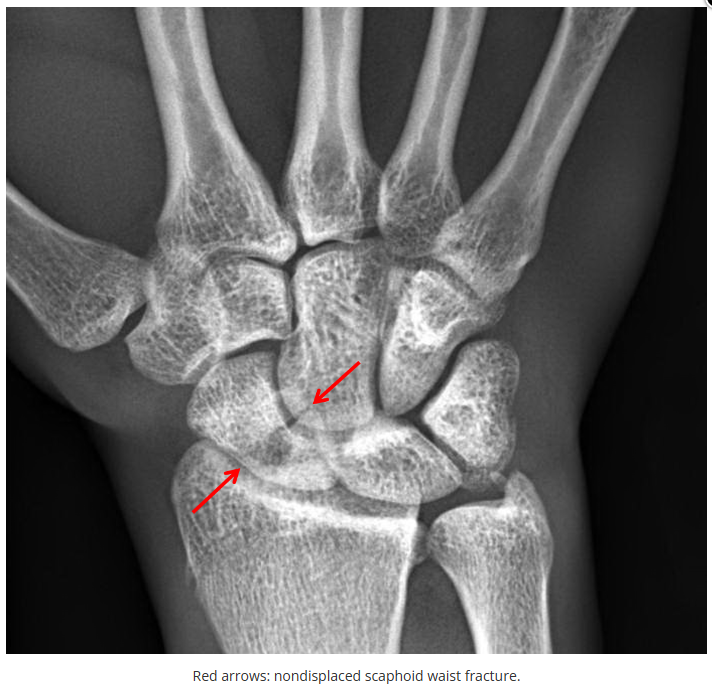

这些腕与手的骨折X线片如果没有标注箭头,你还能识别出来吗?

X线读片是骨科医生的基本功。

今天是腕部与手的X线片。所有X线片都

带有标注和说明

,可以选择长按图片,

自动翻译相关说明

。